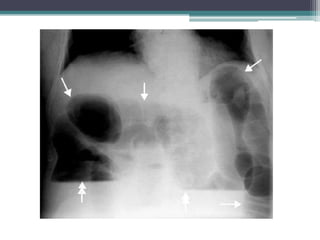

Tài liệu bàn về tắc ruột, bao gồm định nghĩa, phân loại và nguyên nhân của tình trạng này, với sự phân biệt giữa tắc cơ học và cơ năng. Các triệu chứng và chẩn đoán lâm sàng được trình bày, kèm theo phương pháp chẩn đoán cận lâm sàng như x-quang và siêu âm. Ngoài ra, tài liệu cũng đề cập đến các biến chứng và hậu quả của tắc ruột.